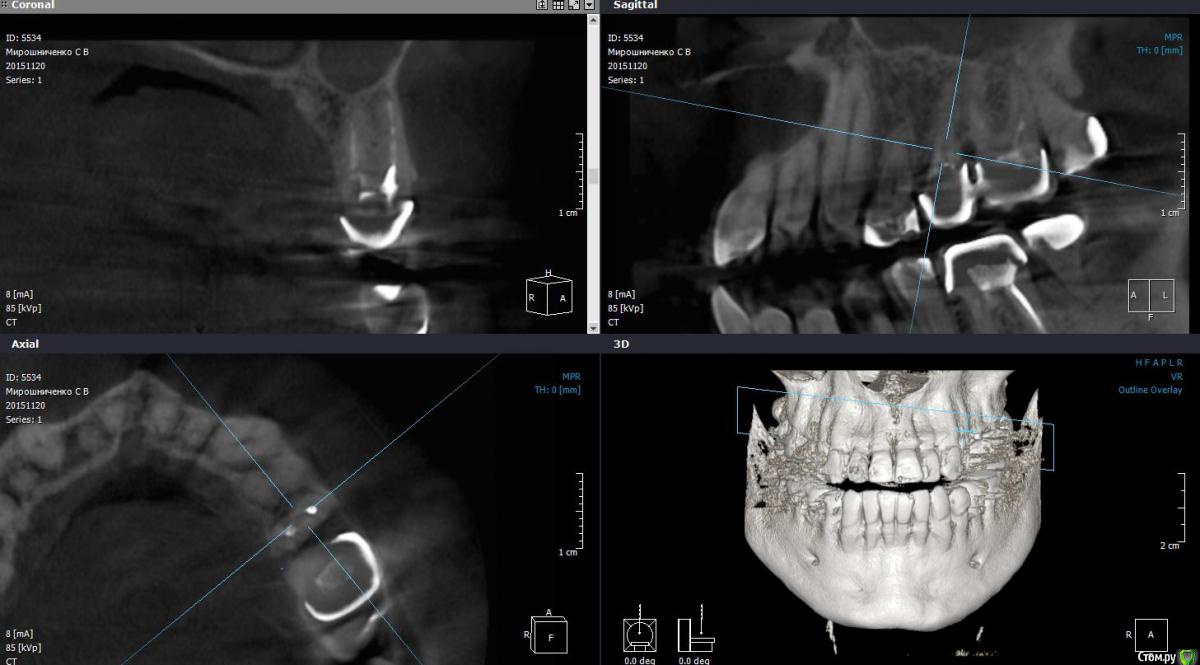

St. Опубликовано 23 марта, 2016 Автор Поделиться Опубликовано 23 марта, 2016 Совсем фейл. Повторное эндо. Сломала на финише профайл 30,04. Вроде обошла 15, но ротари ушла в сторону. Пац обо всем предупрежден. Наблюдаем. Решили не доставать ибо по твердым тканям там и так печаль, если спрямить доступ большая вероятность ленточной перфы. А что бы в таком случае сделали вы? 3 Ссылка на комментарий